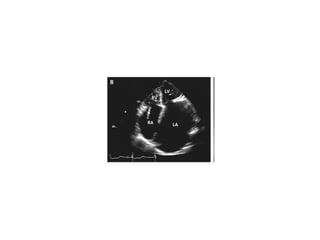

83 years old lady chronic AF , Dysphagia

Echocardiogram showed massive biatrial enlargement (left larger than right),

An 83-year-old woman with long-standing atrial fibrillation who had previously undergone atrioventricular nodal ablation and pacemaker placement presented with symptoms of progressive heart failure. The patient was discharged home on medical management after prolonged diuresis.